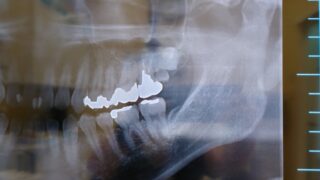

下の写真の患者様は左上に小さな過剰歯とその下に後ろに傾斜した埋伏智歯がありました。過剰歯は歯肉炎を起こしていて感染が埋伏している親知らずに波及している可能性がありました。

親しらずの埋伏方向を確認するためにCT撮影を実施いたしました。CTでは明らかに親知らずが後ろを向いているのが分かります。